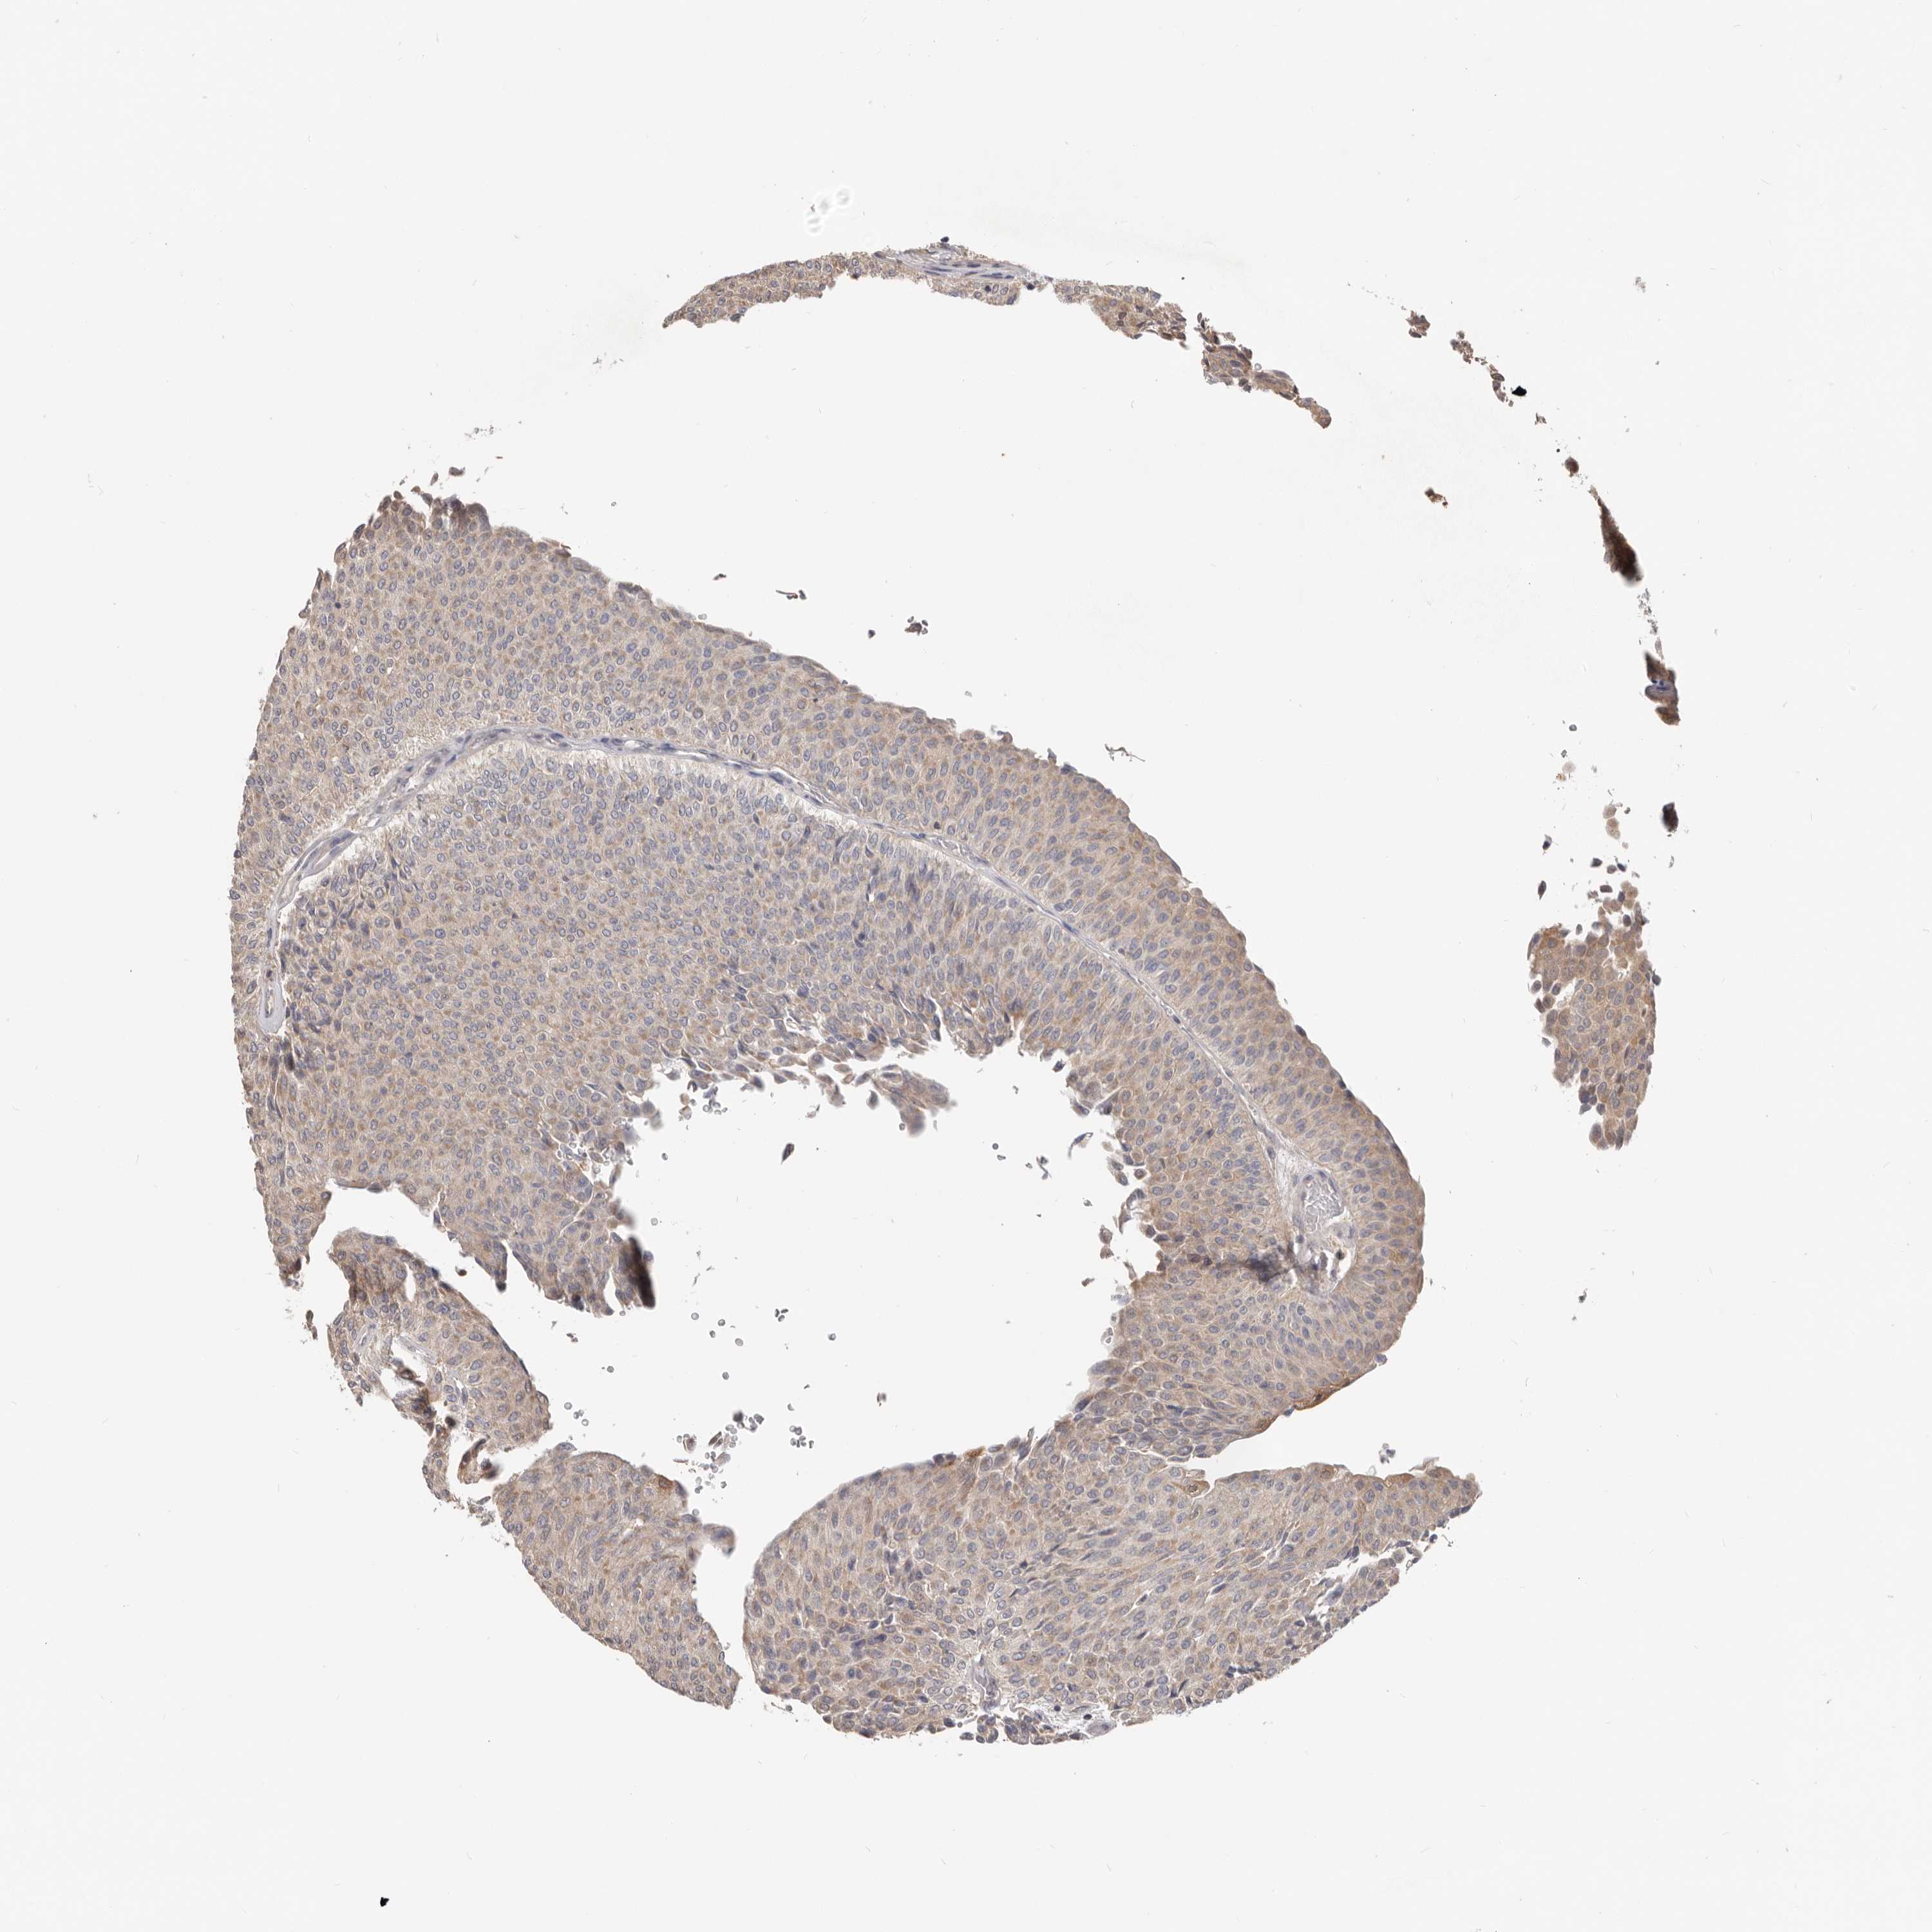

UROTHELIAL CANCER - Protein expressioni

A mouse-over function shows sample information and annotation data. Click on an image to view it in a full screen mode. Samples can be filtered based on level of antibody staining by selecting one or several of the following categories: high, medium, low and not detected. The assay and annotation is described here.

Antibody stainingi

Antibody staining in the annotated cell types in the current human tissue is reported as not detected, low, medium, or high, based on conventional immunohistochemistry profiling in selected tissues. This score is based on the combination of the staining intensity and fraction of stained cells.

Each image is clickable and will lead to virtual microscopy that enables deeper exploration of all samples and also displays staining intensity scores, fraction scores and subcellular localization as well as patient and tissue information for each sample.

Antibody HPA029925

Antibody CAB004490

Urothelial carcinoma, Low grade

Urothelial carcinoma, High grade